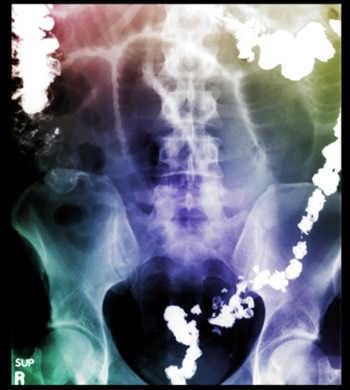

Lo que nadie sabía era que después de la colonoscopía el intestino se deslizó sobre sí mismo al retirar el endoscopio, formando una especie de manga sobre si mismo y progresivamente se fue obstruyendo más y más al avanzar rumbo a la porción más distal del colon, (sigmoides y recto), generando una severa obstrucción.

Cuando la vimos el siguiente grupo de médicos, distinto al que inició su estudio, las evidencias en su evolución, no nos podían explicar cómo los primeros no habían visto la obstrucción en la colonoscopía, y cómo no podían haberse dado cuenta de la obstrucción desde antes, pensando que esto estaba desde el inicio y que en realidad era un tumor que bloqueaba el paso al contenido intestinal en el colon.

Después de 48 horas las cosas comenzaron a funcionar, descubrimos que el problema no era un tumor sino una intususcepción, proceso raro pero de mejor pronóstico que estaba resuelto y que le daba más oportunidades de recuperación. Así en ese momento y con más ganas que nunca decidimos luchar por su bienestar, alimentándola por vía intravenosa y aportando todo lo que hacía falta para llevarla a un estado de bienestar.